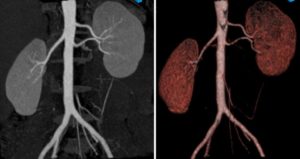

По степени информативности МРТ или КТ сканирование почек значительно опережает стандартные обследования с помощью УЗИ, показывая любые аномалии развития, патологии и воспалительные очаги. Внешне аппараты для томографии выглядят идентично, но в основе положен разный вид излучения.

- МРТ соединяет свойства электромагнитного поля. Оно передает информацию в виде высокочастотных импульсов, которые компьютер считывает в виде четких срезов толщиной не более 1–2 мм. Последние модели сканеров формируют трехмерное изображение почки с прилегающими кровеносными сосудами, что необходимо при сложных операциях, трансплантации.

КТ и МРТ почек — это высокоточные визуализационные методы исследования. КТ почек — это рентгенологический метод исследования, методика которого базируется на возможности объемной визуализации тканей и проектировании данных на экран компьютера. КТ почек бывает без использования контраста и с использованием йодсодержащего контраста для лучшей визуализации сосудов и тканей.

МРТ почек — это визуализационный метод исследования, который базируется на использовании магнитных полей высокой, средней и низкой напряженности.

Отличия КТ и МРТ почек заключаются в разнице их физической природы, от которой зависит степень визуализации той или иной ткани.

К примеру, КТ почек позволяет визуализировать кальцинаты и солевые отложения, что делает этот метод более подходящим для диагностики мочекаменной болезни и камней в почках.

Кроме этого, КТ хорошо подходит для диагностики опухолевых процессов в почках, метастазов в регионарных лимфоузлах и близлежащих органах. МРТ, в свою очередь, позволяет различить разные ткани органа (корковый и мозговой слои), что связано с разной восприимчивостью тканей к магнитным волнам.

- При проведении магнитно-резонансной томографии применяются свойства магнитного поля и радиочастотных импульсов. При этом получаются 3D изображения исследуемого органа, которые показывают наличие патологии и ее локализацию.

- Компьютерная томография проводится благодаря сочетанию принципа диагностики лучевого типа (рентгеновское излучение) с современными компьютерными технологиями. В результате получают послойное изображение органа во множестве срезов.